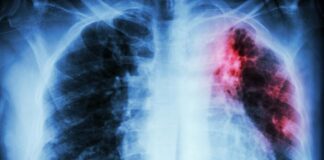

Ölkəmizdə vərəmlə bağlı statistika AÇIQLANDI

Mart 11, 2026 15:00